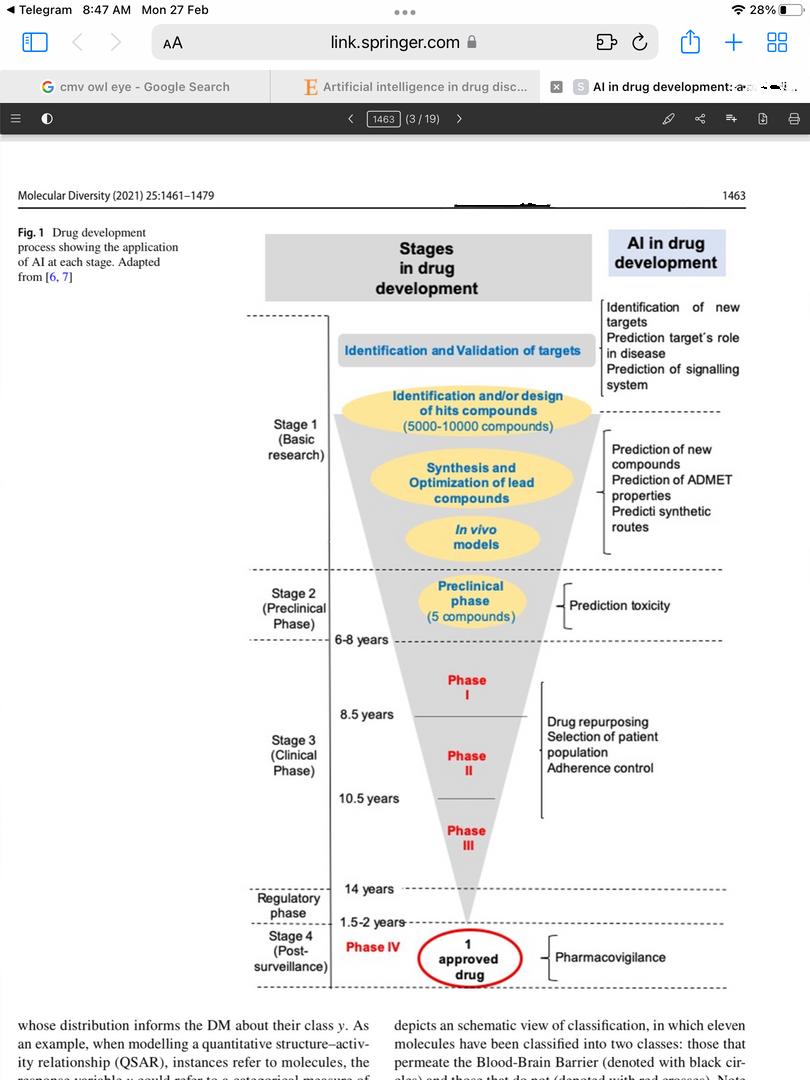

In spite of its many benefits, artificial intelligence (AI) is currently confronted with a number of significant data challenges, including the scale, growth, diversity, and uncertainty of the data. The data sets that pharmaceutical companies have available for drug development can involve millions of compounds, and the traditional ML tools that are used may not be able to handle the complexity of this type of data. A computational model that is based on the quantitative structure-activity relationship (QSAR) can quickly predict large numbers of compounds or simple physicochemical parameters like log P or log D On the other hand, these models are a long way from being able to predict more complicated biological properties, such as the efficacy and adverse effects of compounds In addition, models that are based on QSAR are plagued by issues such as having insufficiently large training sets, having experimental data in training sets that is inaccurate, and not having sufficient experimental validations. The recently developed AI approaches, such as deep learning (DL) and relevant modelling studies, which can be implemented for safety and efficacy evaluations of drug molecules based on modelling and analysis of big data, can help overcome the challenges that have been presented here. Various AI tools are being used to aid in all four stages of the drug development process (basic research for drug discovery; pre-clinical phase; clinical phase; and postmarketing).

Identifying molecular targets, searching for hit and lead compounds, synthesising drug-like compounds, and predicting ADME-Tox are some of the main tasks where AI has proven useful. On the one hand, this review brings a mathematical vision of some of the key AI methods used in drug development closer to medicinal chemists, while on the other hand, it brings the drug development process and the use of various models closer to mathematicians The emphasis is on two aspects that are not covered in other surveys: Bayesian approaches and their applications to molecular modelling, and the eventual final use of the methods to support decisions.